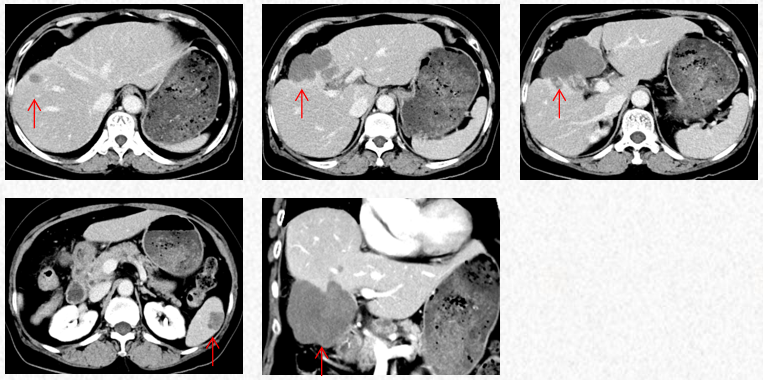

2023-3-19复查胸腹CT图片,最佳疗效评估为PR。

2023-5-22复查胸腹CT图片,疗效评估为SD,出现轻度双上肢麻木,可耐受。

2023-3-19胸腹CT:肝肿物最大横截面积91*60mm,脾脏转移瘤(19*12mm)

2023-5-22胸腹CT:肝肿物最大横截面积86*58mm,脾脏转移瘤(19*12mm)